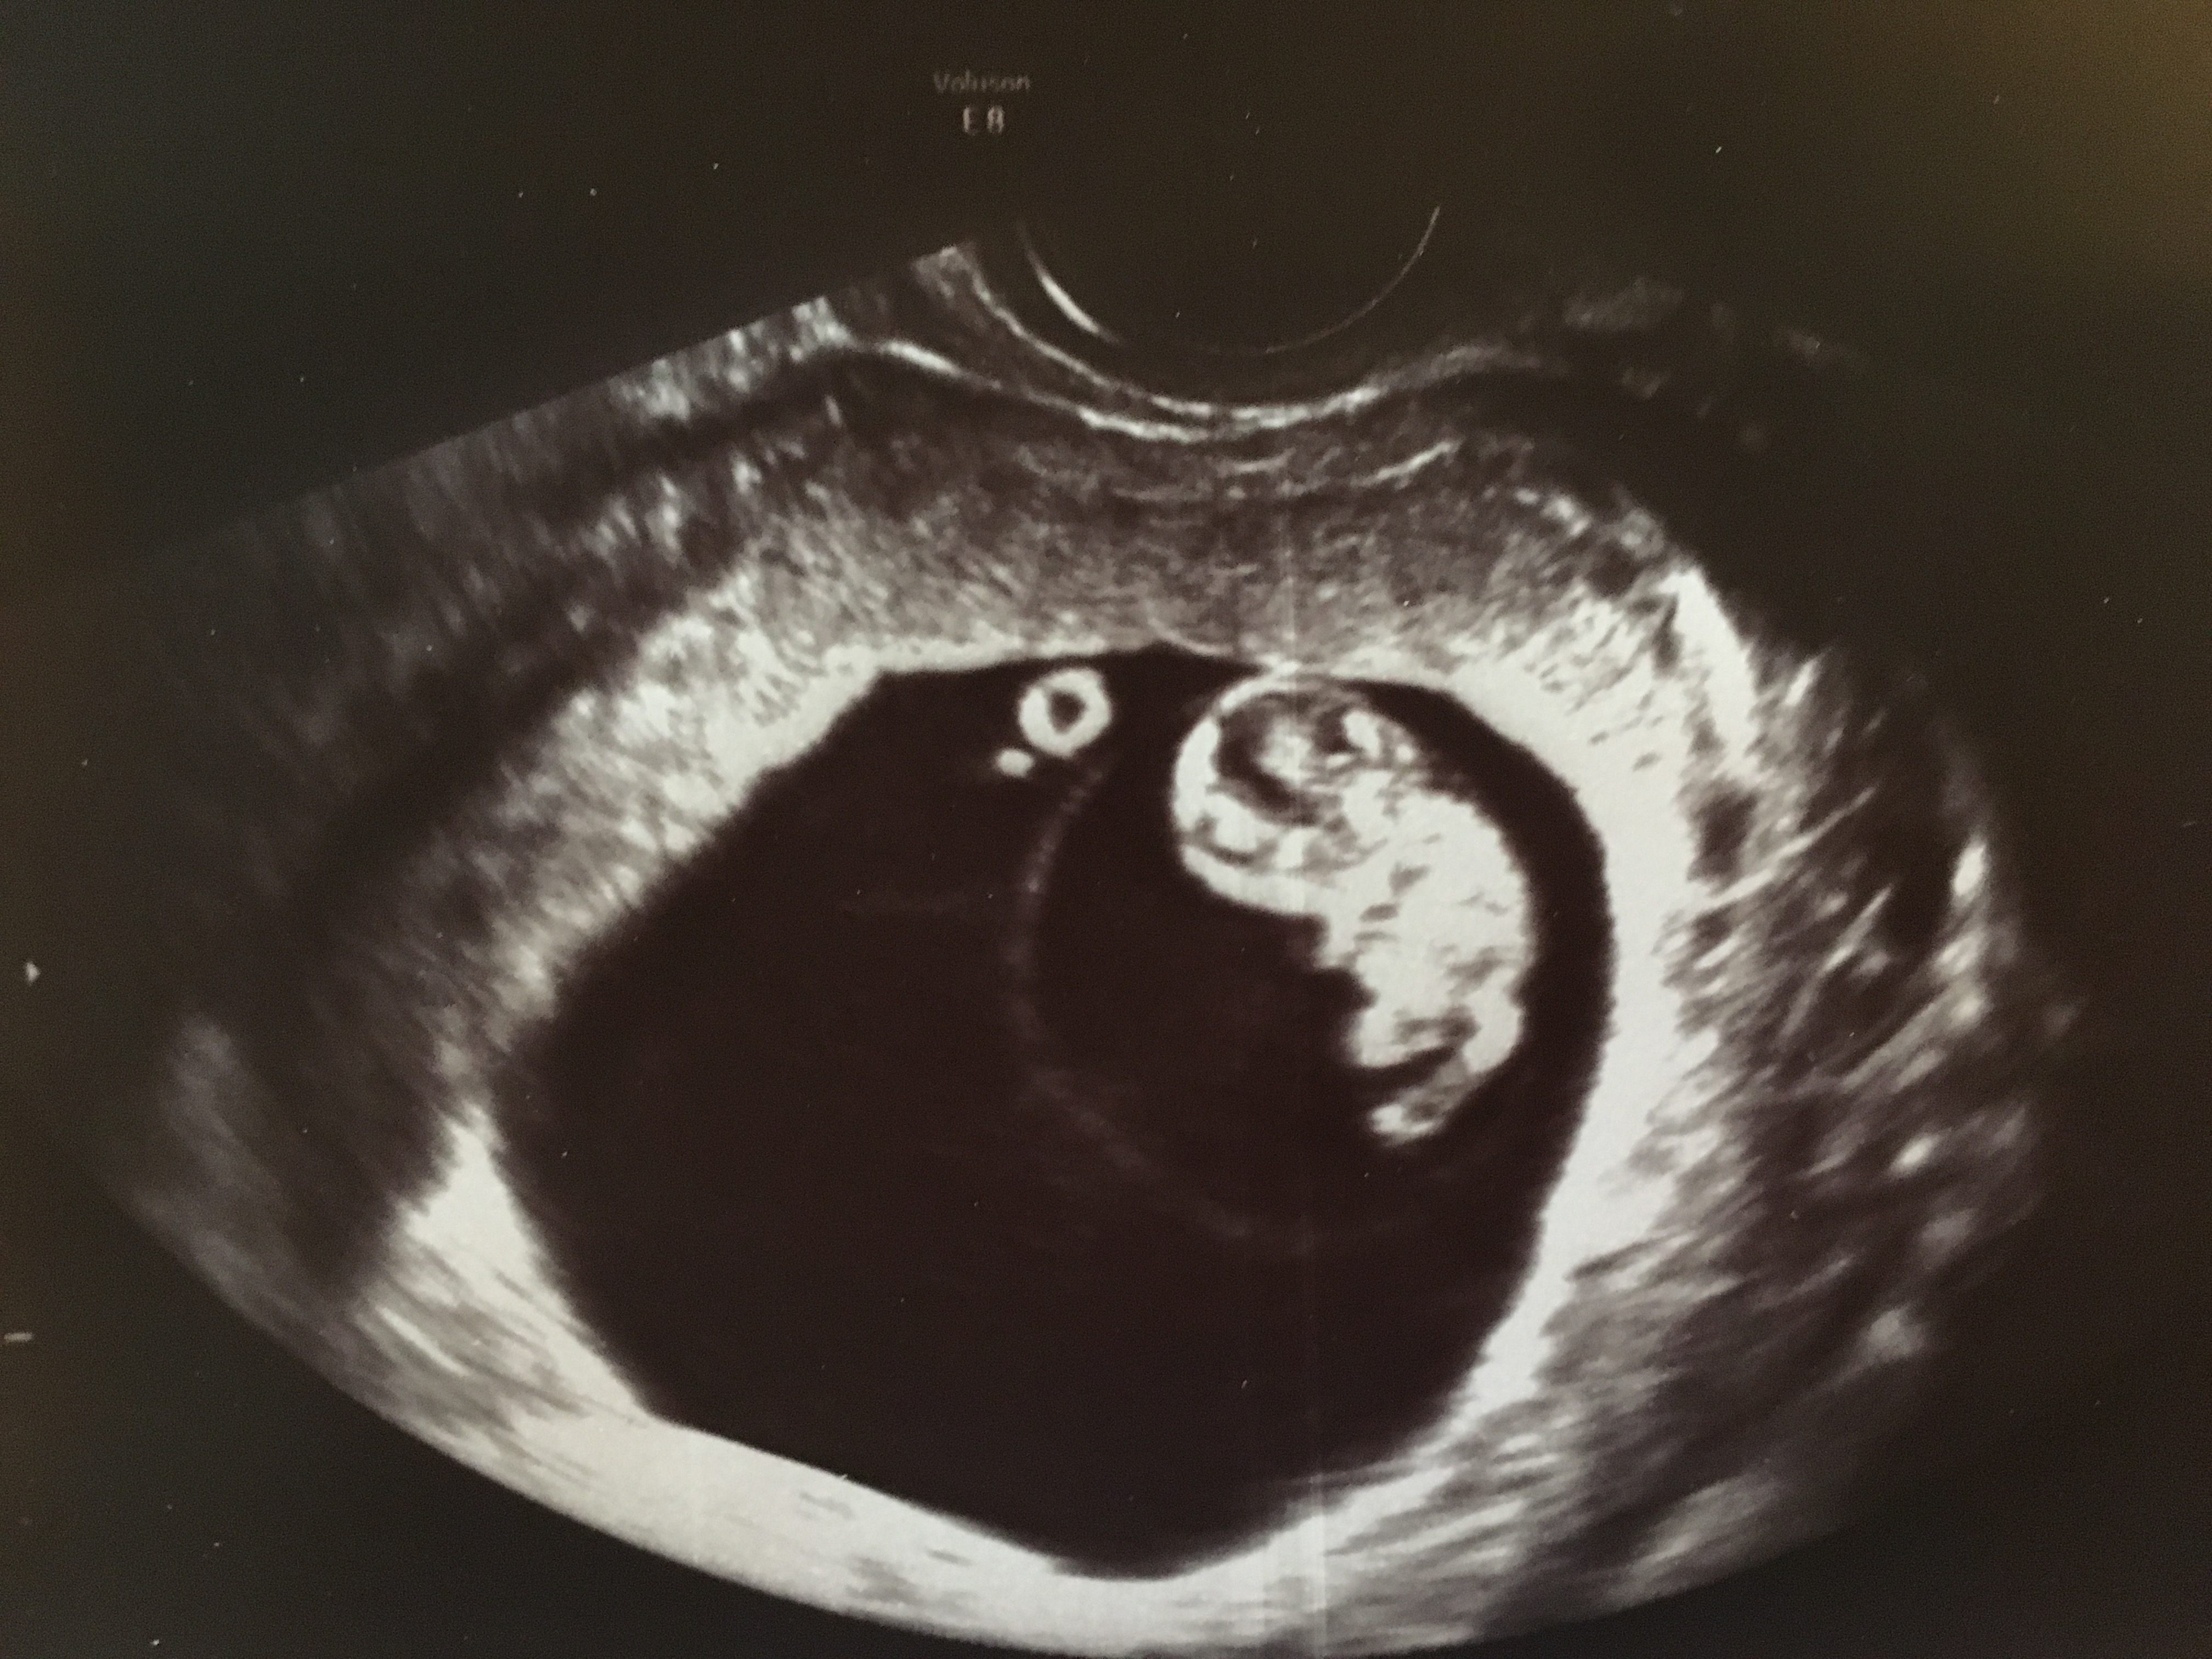

My first ultrasound pic at 9w3d. Measured a few days small. Doctor pointed out that I had twins, but one was not able to stick around We're sad about this, but we're thrilled to see our other healthy little baby! So in love!

So sorry you lost one but happy to hear you still have a healthy baby!